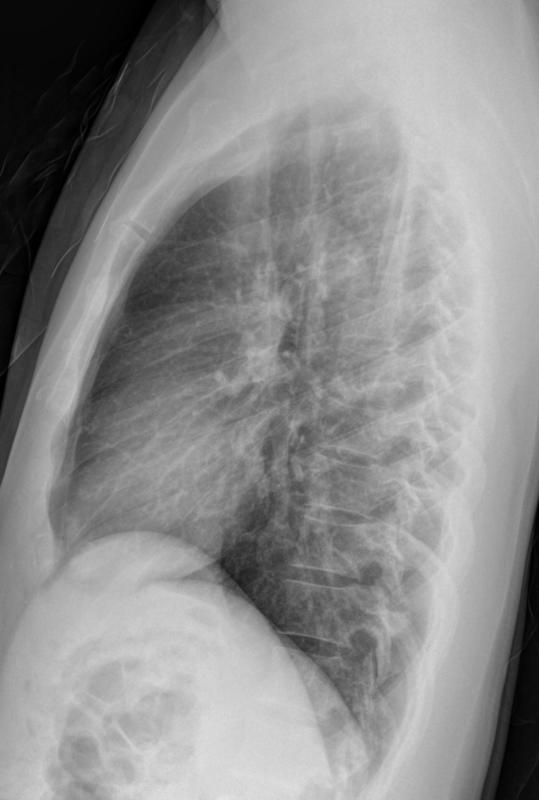

Normal  lateral

24 yo male